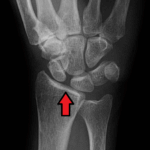

[doctormodu]1 lichtman classification - lunate AVN

07 월상골 무혈 괴사(Lunate AVN) Kienbock’s disease